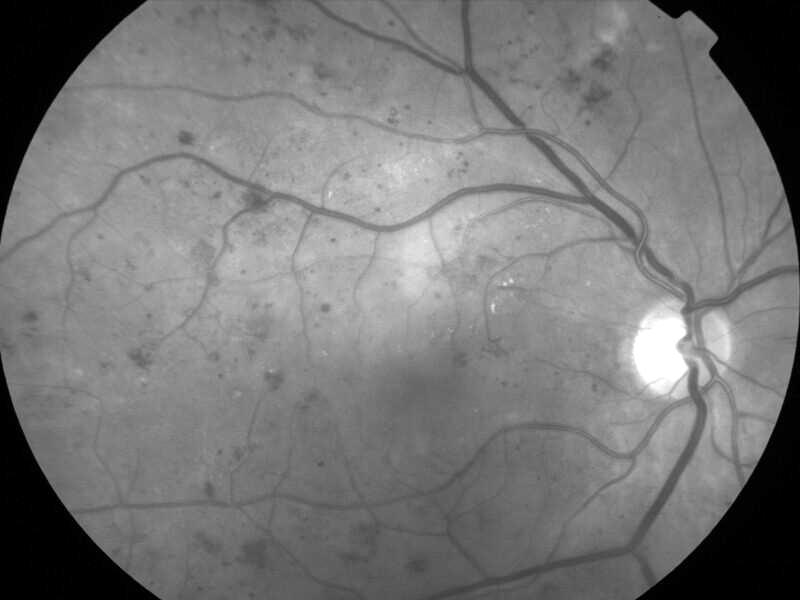

rétinopathie diabétique pré-proliférante